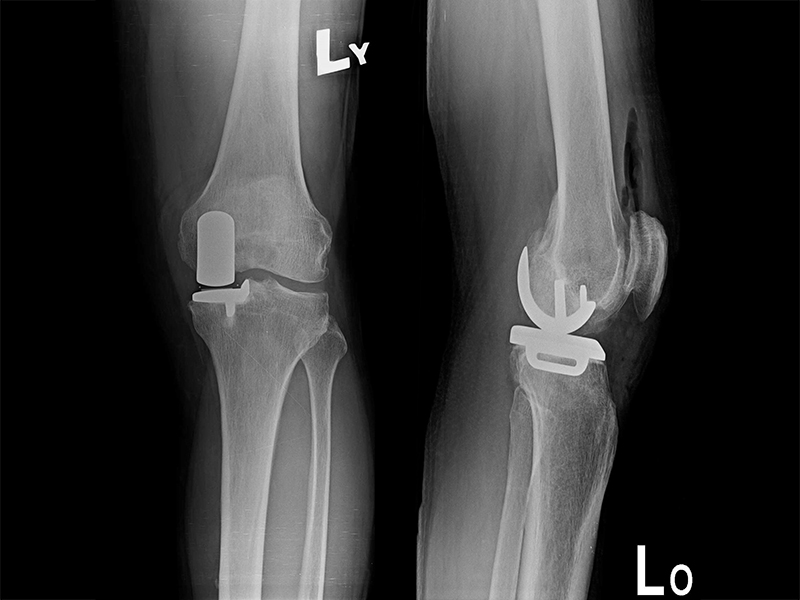

膝關節手術